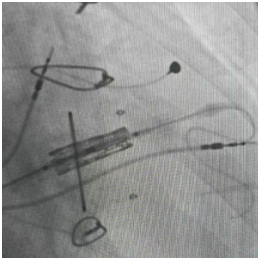

经过心脏外科、心内科、麻醉科、超声科等多学科反复论证,团队最终决定:采用经导管介入技术,一次性完成三大操作——球囊扩张狭窄的三尖瓣、植入新的生物瓣、同时安置永久起搏器。

球囊扩张术

“这相当于用微创的方式,完成过去需要三次手术才能解决的问题。”陈文生主任解释说,介入操作无需再次开胸,只需通过血管穿刺送入导管,对患者创伤小,尤其适合这种多次手术后的高危患者。

手术台上,心脏大血管外科陈文生团队通过细致的影像引导,将球囊送至原有瓣膜处进行扩张,随后将新的生物瓣精准释放在预定位置。最后,在心脏稳定的状态下,顺利植入了永久起搏器。整个过程中,患者生命体征平稳。